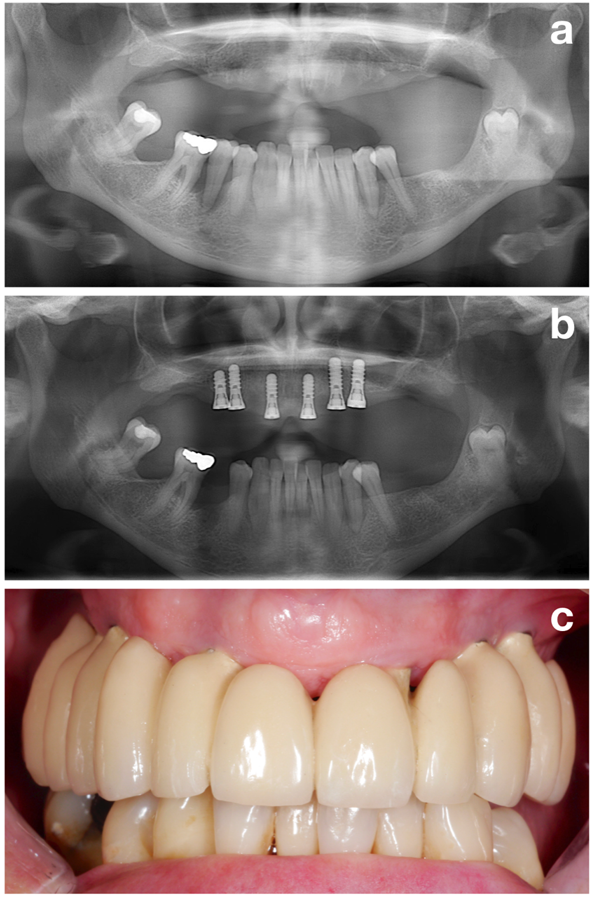

In conclusion, establishing a stable periodontal situation is next to other aims, such as smoking cessation or perfect oral hygiene (Figure 3), one of the most important goals in the pre-treatment phase, which should be achieved prior to implant installation!